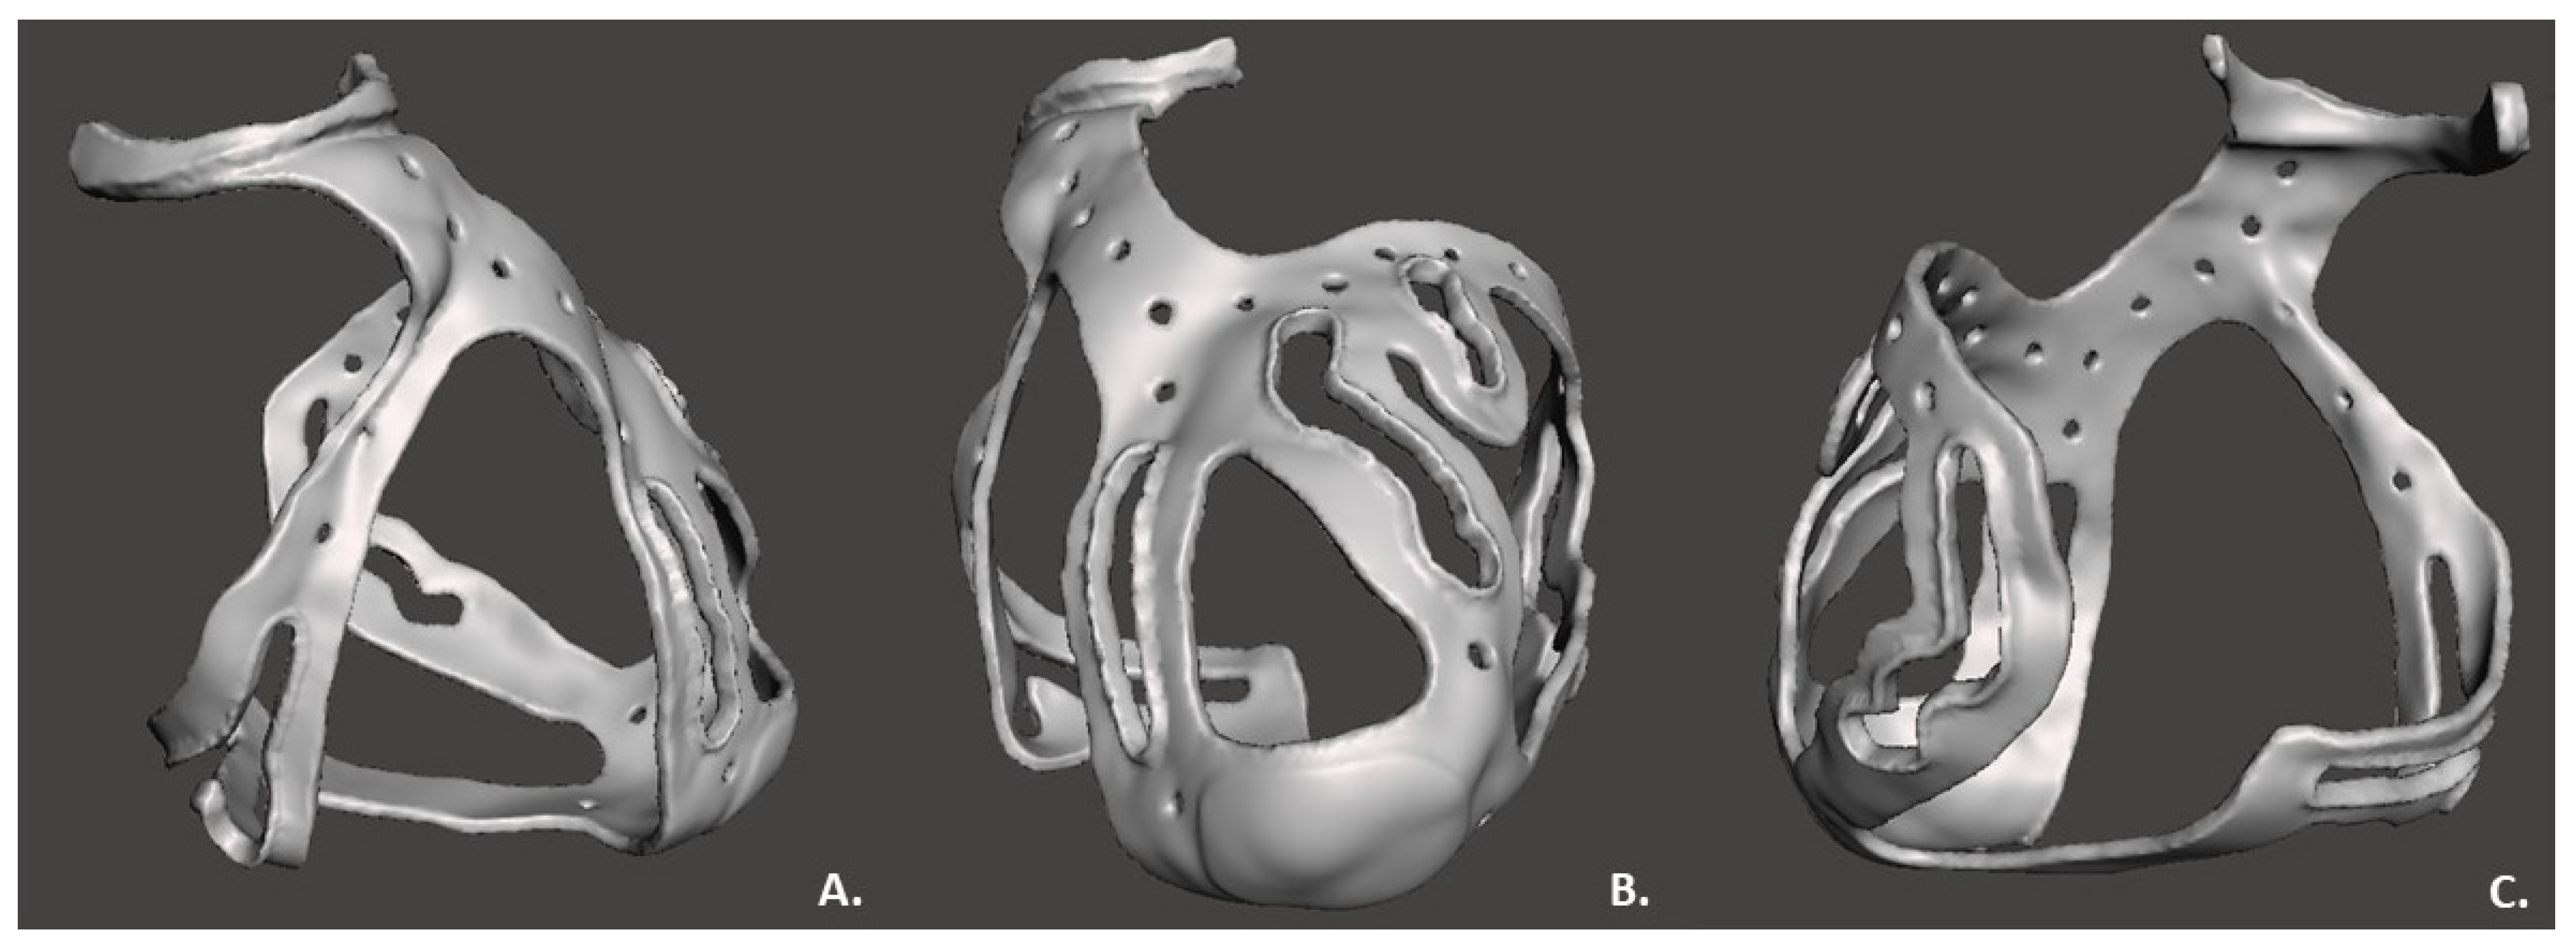

2.2. 3D Surgical Prototype Design

3. Results